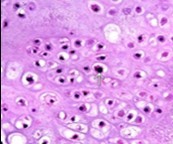

Figure 5.Enchondroma enunciating lobules of uniform cartilaginous cells with regular, centric nuclei and absence of mitosis 13.

Enchondroma enunciating             lobules of uniform cartilaginous cells with regular, centric nuclei and absence of        mitosis 13.